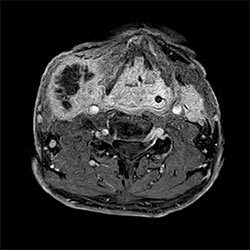

In a society where reimbursements are declining and chronic conditions lead to increased MR procedures and longer waiting times, there is ever increasing pressure on the radiology department. Today, further attempts to accelerate, compromise image quality or are limited to a narrow range of scans. Therefore, to meet the increased demand for productivity, a technology break-through in acceleration is still required. Leveraging our long standing leadership position in speed (i.e. SENSE), Philips brings compressed SENSE, a breakthrough in productivity.

Compressed SENSE increases the examination efficiency thanks to a shorter scan time with no change in image quality”

Sachi Fukushima, RT, Kurashiki Central Hospital, Japan

Learn more about the main principles of Compressed SENSE and how it introduces a paradigm shift in productivity, how Compressed SENSE was designed around image quality, and how it advances productivity for clinical MR imaging.